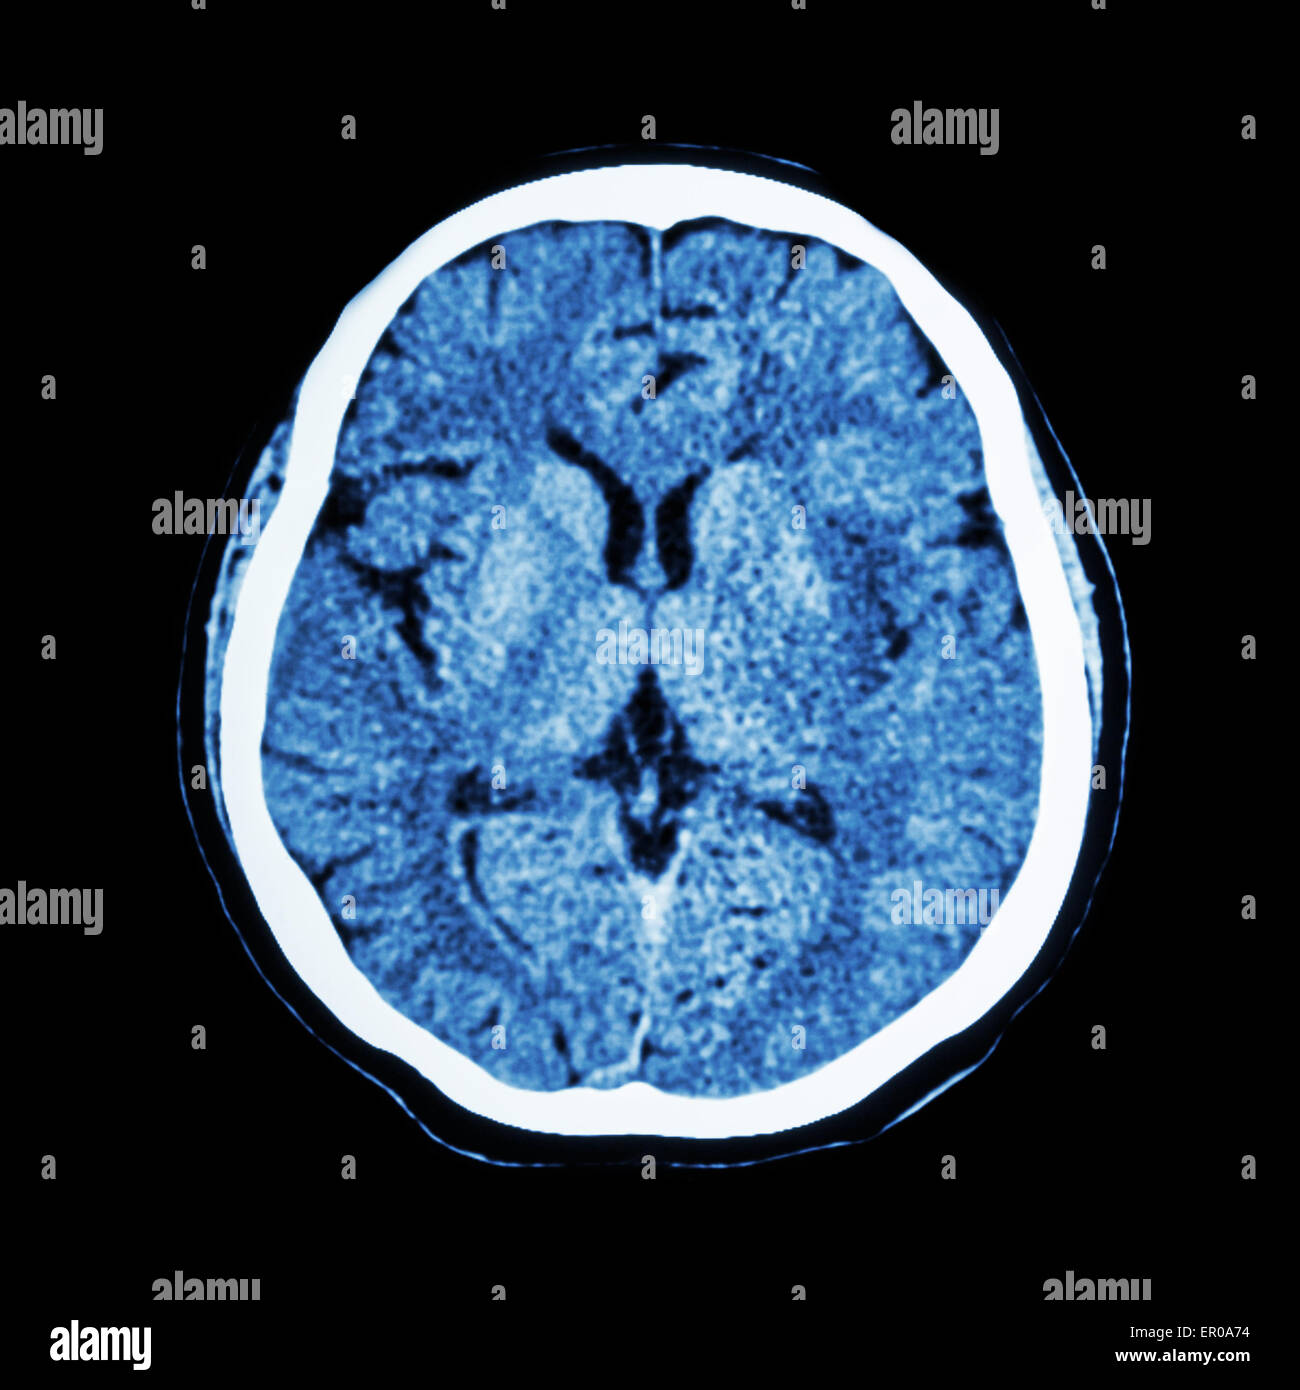

CT scan de cerveau : montrer l'humain normal CAT scan ( cerveau ) Banque D'Imageshttps://www.alamyimages.fr/image-license-details/?v=1https://www.alamyimages.fr/photo-image-ct-scan-de-cerveau-montrer-l-humain-normal-cat-scan-cerveau-82986600.html

CT scan de cerveau : montrer l'humain normal CAT scan ( cerveau ) Banque D'Imageshttps://www.alamyimages.fr/image-license-details/?v=1https://www.alamyimages.fr/photo-image-ct-scan-de-cerveau-montrer-l-humain-normal-cat-scan-cerveau-82986600.htmlRFER0A74–CT scan de cerveau : montrer l'humain normal CAT scan ( cerveau )